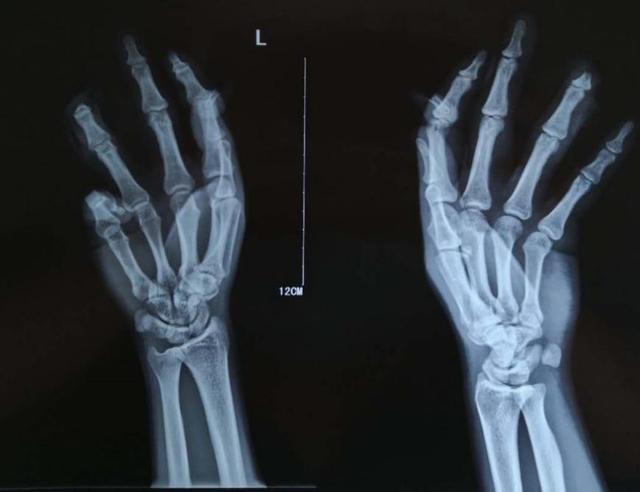

找到血管和神经之后,确定手术可以顺利的继续进行,便可以先用一根钢针(医生们称之为克氏针)把断掉的骨头重新连接起来固定好,通过X光,我们可以确定骨头的位置和钢针的位置正确,之后,便到了整个手术最重要的阶段——把断掉的血管和神经再接起来。